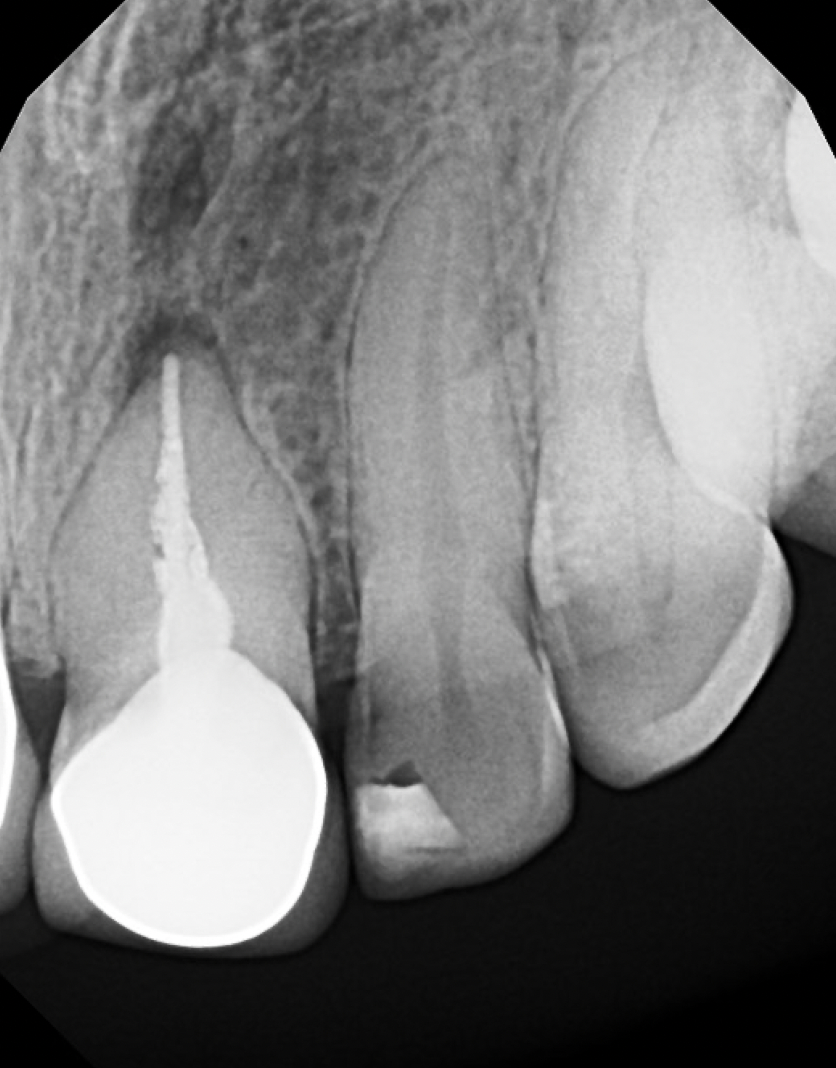

#10 S-RCT

Dx: Previously Treated with CAA